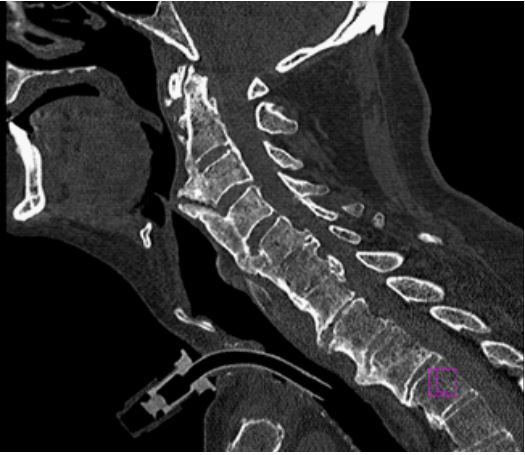

Due to the lack of improvement in swallowing function, a fiberoptic endoscopic evaluation was performed (Figure 1): a severe anteriorization of the posterior pharyngeal wall was coming into contact with the epiglottis with consequent reduction of the lumen and marked stagnation of secretions. To investigate the causes of pharyngeal stenosis, an x-ray of the cervical spine was performed (Figure 2). The x-ray showed anterior cervical osteophytes at C3, C4, C5 and C6; therefore, computed tomography was carried out (Figure 3). Osteophytic alterations with a tendency towards bridging fusion in the C2-C5 tract was described. Coarse ossification of the anterior longitudinal ligament with evidence of a spur shaping an acute angle at the level of the epiglottis, significantly imprinted the posterior wall of the hypopharynx and determined a clear focal reduction in the calibre of the lumen. The diagnosis of ankylosing spondylitis, infection and malignancy were ruled out and Forestier Disease was confirmed.

Figure 3: Computed Tomography.